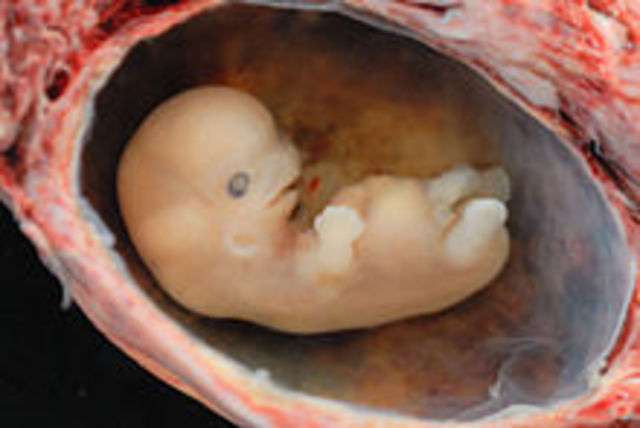

Embryo- A unborn offspring in the process of development, during the period from approximately the second to the eighth week after fertilization.

• 2nd Month

2nd Month

6 weeks:

1. 5/8 inches long.

2. Eyelids form.

3. All organs developed.

8 weeks:

1. Bones and muscles developing.

2. Leg buds start to grow.

3. Arm buds start to grow.